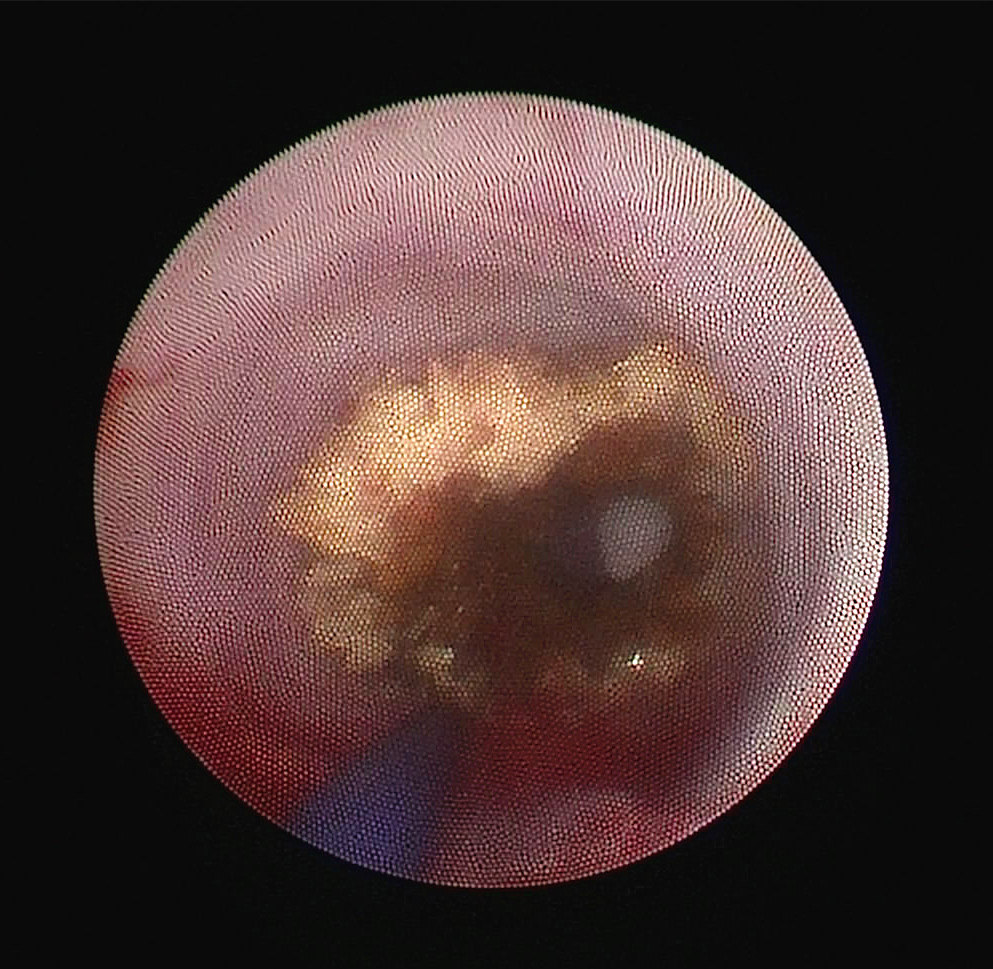

术中输尿管镜下发现右输尿管结石由于梗阻时间太长,已被息肉包裹,引起输尿管完全梗阻

![1497442499888454.jpg 2017-06-14_1202[00_08_07][20170614-195328-1].JPG](https://content-resource.91160.com/resource/160jmxhdf/200417607/331037/41.jpg)

予以钬激光将结石粉碎,完全恢复右输尿管的连续性,但由于就诊太晚,预后很差,日后血透治疗已不可避免